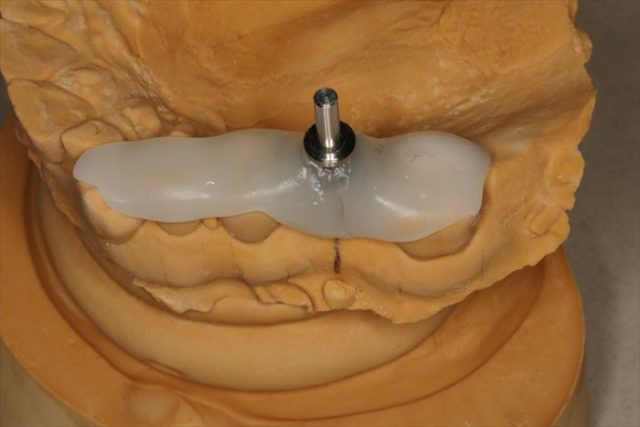

上下歯列模型の印象採得とフェイスボウトランスファーをいつものように行い、下顎の回転半径の近似値を得ます。

半調節性咬合器に上下歯列模型をフェイスボウを用いてマウントしました。

模型とCTデータを重ねて埋入ポジションを決定します。

術者の脳内イメージを作成する行程です。

サージカルステント(ドリルガイド)を製作してオペ前の準備は完了です。